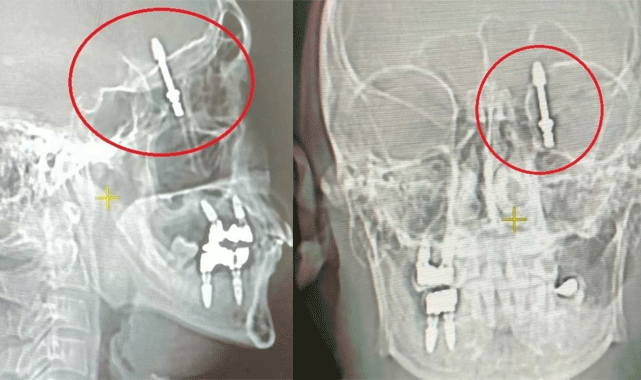

Nilüfer ilçesindeki özel bir diş kliniğinde çalışan fabrika işçisi ve 2 çocuk babası Ramazan Yılmaz (40), diş ağrıları nedeniyle doktora gitti. Doktor A.D., Yılmaz'a dişlerinin sallandığını ve çekilmesi gerektiğini belirtti. Yılmaz, doktorun önerisi üzerine çekilen dişi yerine implant yapılması için tedaviyi kabul etti. Ancak işler planlandığı gibi gitmedi. İmplant operasyonu sırasında yaşanan bir hata sonucu vidanın çene kemiğine saplanmasıyla Yılmaz'ın sağlığı ciddi şekilde tehlikeye girdi. Şimdi, Yılmaz ve ailesi yaşadıkları kabusun ardından adalet arayışında.İddiaya göre, implant operasyonu sırasında doktorun hatalı müdahalesi sonucu vida, Yılmaz'ın çene kemiğini delerek kafatasına saplandı. Şiddetli acılar içinde baygınlık geçiren Yılmaz'ın durumuyla ilgilenmek yerine film çeken Doktor A.D., vidanın kafatasında olduğunu fark edince hemen Yılmaz'ı kendi aracıyla bir hastaneye götürdü. Hastanede yapılan tomografi sonucunda doktorlar şaşkına döndü ve 2 çocuk babası adamı acil bir ameliyata aldılar. Uzun saatler süren zorlu operasyonun ardından hayata dönen Yılmaz, günlerce hastanede tedavi görmek zorunda kaldı. Sağlığına kavuştuğunda, kendisine yanlış müdahalede bulunan diş hekiminden ödediği ücretin iadesini istedi. Ancak doktorun ret cevabı vermesi üzerine Yılmaz, hukuki yollarla hak arama yoluna gitti.Yaşadığı travmayı anlatan Yılmaz, "Diş ağrılarım nedeniyle Nilüfer'deki özel bir diş kliniğine gittim. Yapılan muayene sonucunda çene kemiğimin zayıf olduğunu ve implant yapılması gerektiğini söylediler. Doktor, kendisinin 24 yıllık tecrübeye sahip olduğunu ve konuda uzman olduğunu iddia etti. Biz de güvenerek kendisine bu işi teslim ettik" şeklinde konuştu.

Uyarılarına rağmen dinlenmediğini dile getiren Yılmaz, "Doktor, işlem sırasında kullandığı cihazın arızalı olduğunu sekreterine bildirdi. Bunun üzerine işlemi el ile yapmaya başladı. Vidayı yerleştirmeye çalışırken, aşırı bir güç uygulandığını fark ettim. Durumu kendisine ilettim ve kemik sesi duyduğumu söyledim. Ancak bana bu durumun normal olduğunu söyledi. Vida çene kemiğimi delerken, göz duvarının arkasında beyin omurilik sıvısının olduğu bölgeye saplandı. Şiddetli acıdan bağırdığımda, ancak o zaman röntgen çektirdi" şeklinde konuştu.